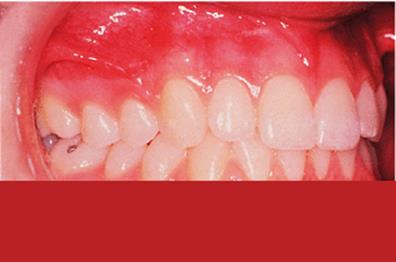

An alternative approach is to correct the upper incisor angulation by moving their crowns labially, which is often straightforward using a removable appliance. The resulting increased overjet and the deep overbite can then be corrected using a functional appliance. This method is particularly appropriate where the lower arch is well aligned. The retroclined upper incisors are often crowded, but this resolves as they are tilted labially into a larger arc. The malocclusion has then been changed from Class II division 2 to a Class II division 1 with aligned arches, which is ideal for treatment with a functional appliance (Fig. 18.3).

Fig. 18.3. (a) Class II division 2 malocclusion with well-aligned lower arch; (b) upper removable appliance to expand the arch and procline the upper incisors; (c) activator appliance in place; (d) some overcorrection was achieved.